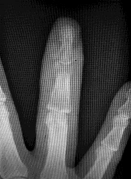

A 6-year-old boy falls on an outstretched hand. Radiographs of the elbow are shown below:

On physical examination, the child is unable to flex the interphalangeal joint of the thumb. Which nerve is most likely injured?

Explanation

The inability to flex the interphalangeal joint of the thumb indicates an injury to the flexor pollicis longus (FPL), which is innervated by the Anterior Interosseous Nerve (AIN). AIN neuropraxia is the most common nerve injury associated with extension-type supracondylar humerus fractures.